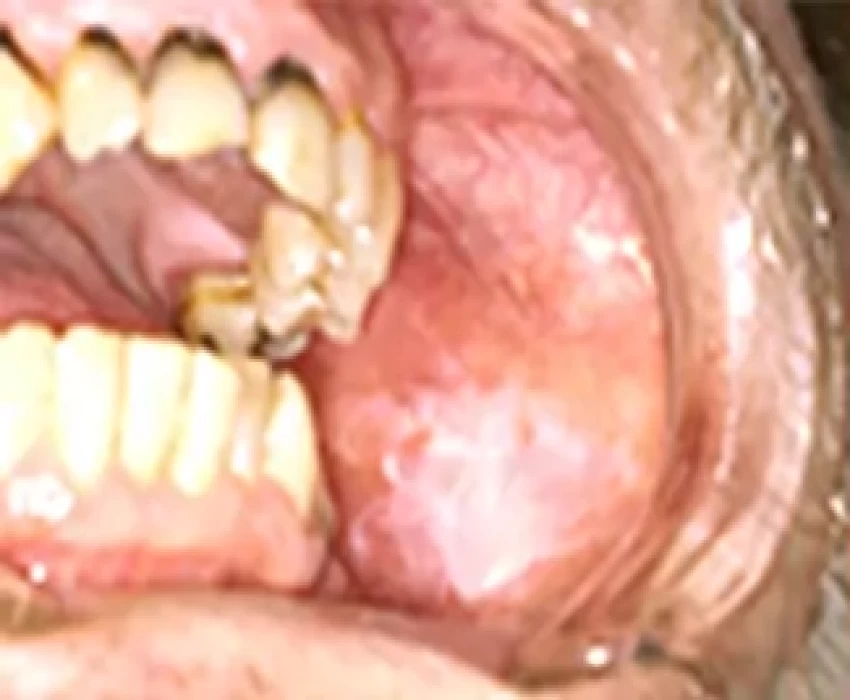

Certain OPMDs, such as oral submucous fibrosis, are encountered particularly with specific lifestyle habits. The main objective is secondary prevention by early detection of PMDs when they can be treated most effectively. PMDs are often undiagnosed due to lack of public awareness and due to lack of knowledge among medical professionals. Clinical appearance and diagnosis of a lesion is not adequate to determine its premalignant nature as not all white lesions turn malignant. Diagnostic biopsy and histopathological examination should be considered for any mucosal lesion that persists for more than 14 days after obvious irritants have been removed. Prognosis and patient survival is directly related to stage and grade of cancer at initial diagnosis. He has a keen interest in the management of Potentially Malignant Disorder